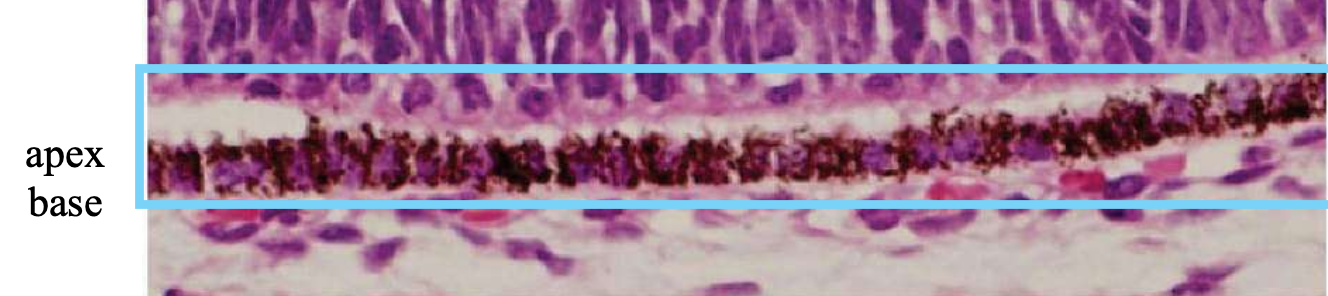

Describe the development of the RPE.

1) Cellular structures and melanosomes begin to appear in the outer layer of the optic cup

Melanosomes: melanin-producing cells inside RPE

2) After week 6, the RPE is 1 cell thick, where they’re cuboidal to columnar

Base of each RPE cell = external toward the developing choroid

Apex of each RPE cell = internal toward the inner layer of the optic cup